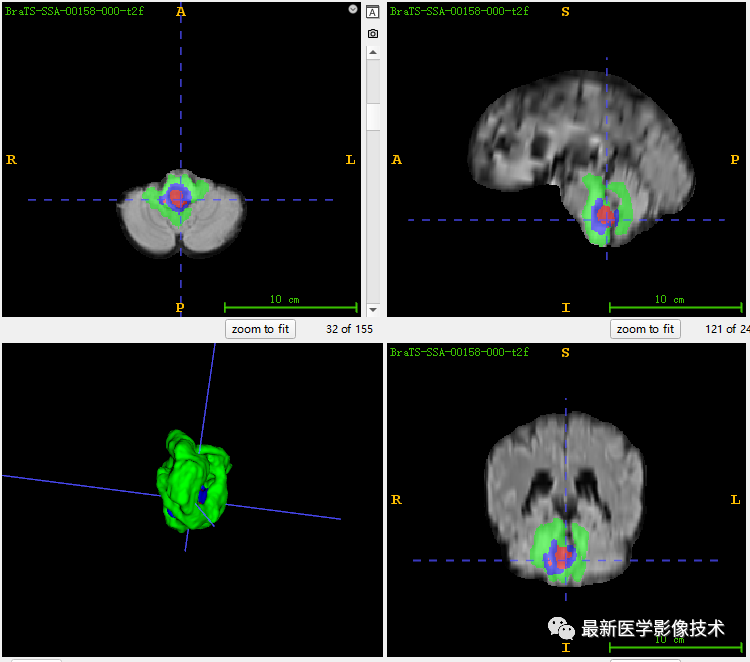

6、验证集分割结果

左图是金标准结果,右图是网络预测结果。

7、测试集分割结果